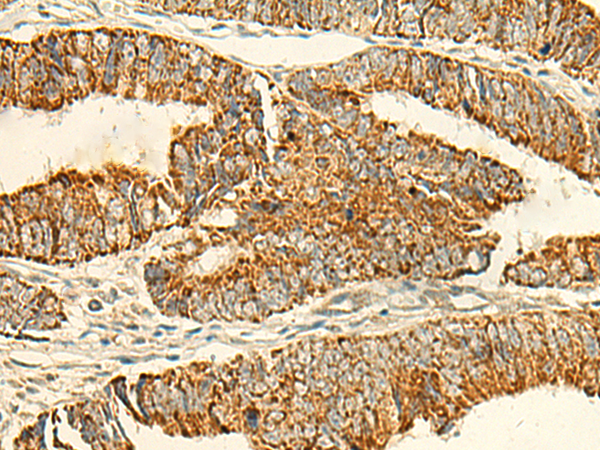

- The image is immunohistochemistry of paraffin-embedded Human tonsil tissue using P10033(IFT27 Antibody) at dilution 1/50. (Original magnification: ×200)

- The image is immunohistochemistry of paraffin-embedded Human colorectal cancer tissue using P10033(IFT27 Antibody) at dilution 1/50. (Original magnification: ×200)